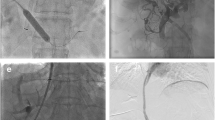

Based on preoperative imaging evaluation and under ultrasound guidance, a percutaneous transhepatic puncture was carried out on the portal venous tributary within the liver. A 5F/6F catheter sheath was then inserted to explore the PV leading to the superior mesenteric vein (SMV) or splenic vein (SV). If entry to the PV or SMV/SV was not successful via a percutaneous transhepatic route, SV splenic tributary was punctured under ultrasound guidance. Subsequently, the catheter wire was directed to the PV or SMV/SV for portal venography. This was done to further confirm the puncture site of the PV and the shunt pathway as well as to measure the PVP. The PV puncture site, known as the B point, is typically found in the extrahepatic portal vein (EPV), the root of the SMV, the hepatic side of the SV, or within the abdominal or retroperitoneal collateral (Fig. 1). When choosing collateral vessels for shunting, it is essential to consider the collateral' diameter, their blood flow direction in relation to the SMV and SV, their distance and spatial relationship with the inferior vena cava, as well as the surrounding tissues (typically the pancreas, intestines, and major vessels). Additionally, a minimum collateral diameter of 6 mm is deemed suitable for shunting, aiming to establish the safest and most direct shunting pathway. The catheter was superselected into the variceal vascular mass of the esophageal fundus, and the variceal vein was embolized using a mixture of spring coil (Interlock, Boston Scientific, USA) and embolization glue (Beijing Kangpaite Medical Equipment Co., Ltd., China)/papaverine ethyl iodide (Hengri Company, China). Subsequently, a pig-tail catheter or balloon with a diameter of 6–8 mm was positioned at the site of the pseudo-puncture, acting as the marker for the PV system's puncture. In addition, in cases where the hepatic artery and the adjacent portal vein are in close proximity, the use of the hepatic artery catheter as a marker can also be considered. If the patient has previously undergone TIPS, the lower end of the original stent can serve as a marker.

A 58-year-old male with Budd–Chiari syndrome, who had previously undergone an inferior vena cava-right atrial shunt and inferior vena cava stent implantation a decade ago, now presents with recurring episodes of esophagogastric variceal bleeding and recurrent ascites. a–b Spiral enhanced CT with multiplanar reconstruction showed cavernous transformation of the portal vein, with the presence of large retroperitoneal collateral vessels communicating with the splenic vein. c Direct portography was conducted through percutaneous splenic puncture, confirming the connection between the target collateral vessels and the splenic vein. d Under fluoroscopy, use the pig-tail catheter as a guide to target the puncture through the IVC. e A stent was successfully placed between retroperitoneal collateral vein and IVC. f The spiral-enhanced CT with multiplanar reconstruction images shows that the stent is patent at 1 month after TEPS. CV collateral vessels, PV portal vein, SV Splenic vein, IVC inferior vena cava